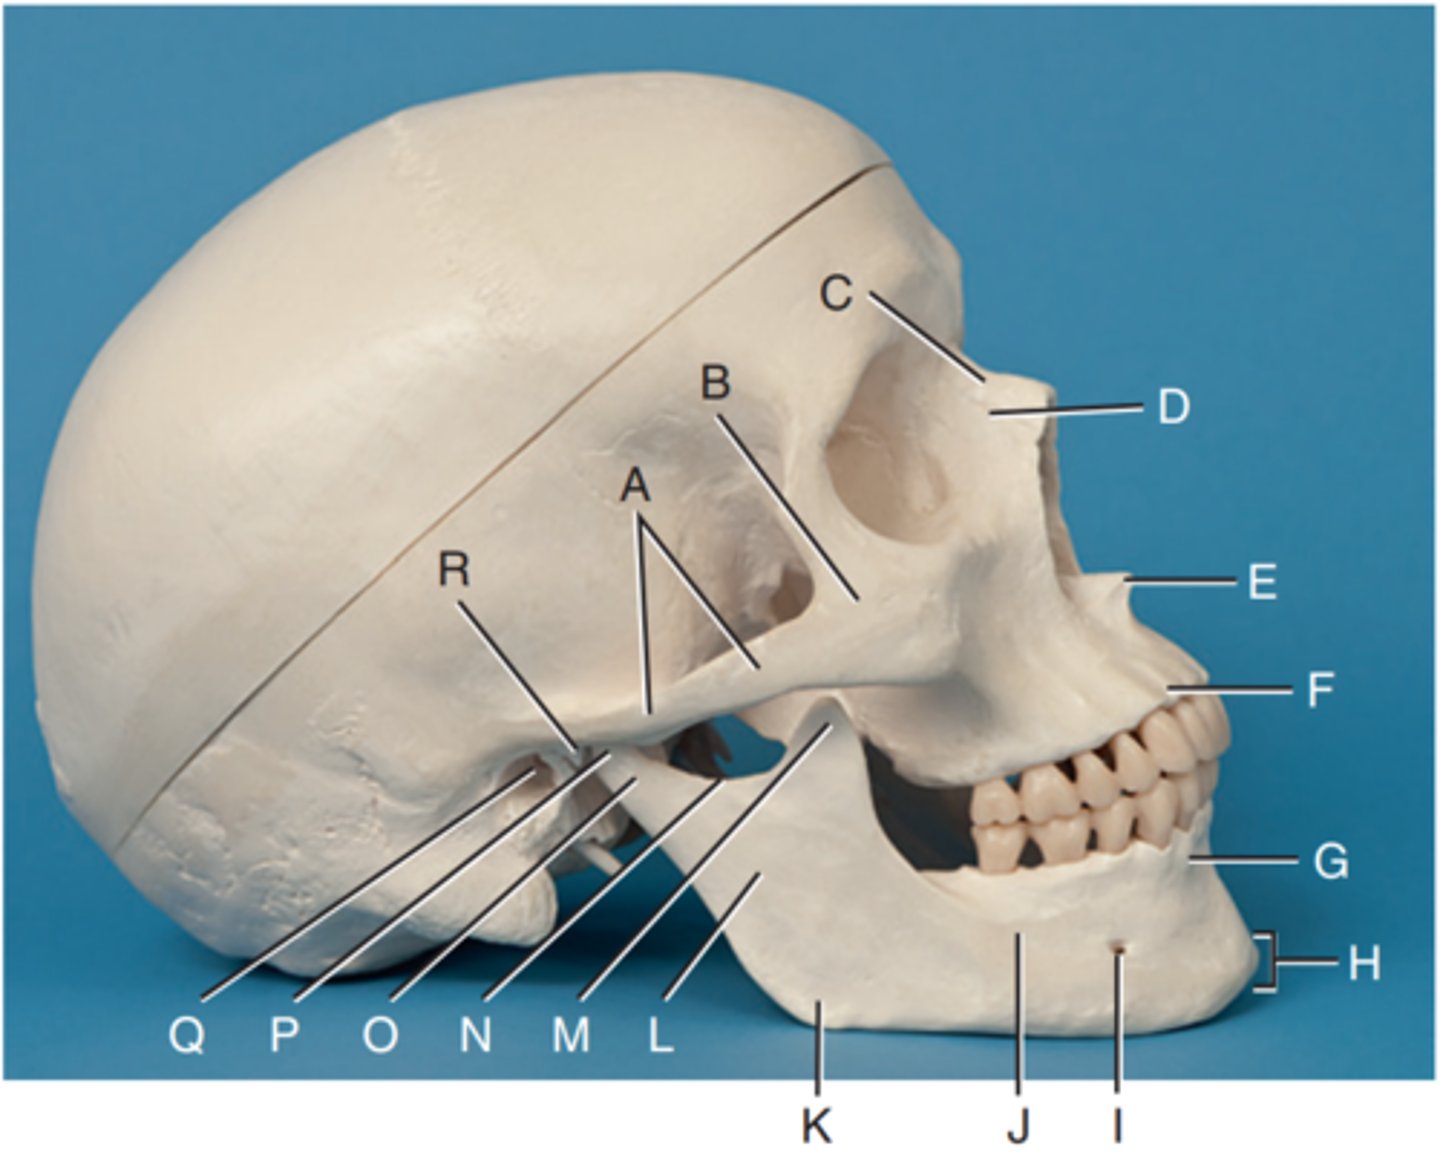

Zygomatic arch

Label A

Right zygomatic bone

Label B

Right nasal bone

Label C

Frontal process of right maxilla

Label D

Anterior nasal spine

Label E

Alveolar process of maxilla

Label F

Alveolar process of mandible

Label G

Mentum or mental protuberance

Label H

Mental foramen

Label I

Body of mandible

Label J

Angle (gonion)

Label K

Ramus of mandible

Label L

Coronoid process

Label M

Mandibular notch

Label N

Neck of mandibular condyle

Label o

Condyle or head of mandible

Label P

EAM

Label Q

TM fossa of temporal bone

Label R